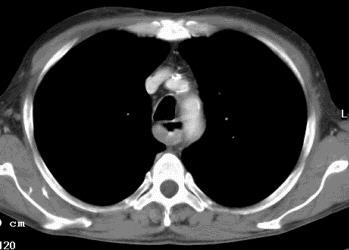

Belüftungsstörungen (Dystelektasen/Atelektasen)Durch reduzierte Atemarbeit (Bettlägrigkeit, Schmerzen bei Rippenfrakturen/-prellungen) sowie Einengung eines zuführenden Luftweges kann es zu Minderbelüftung und damit verbundenem partiellem Kollaps von Lungengewebe, sogenannten Dystelektasen. kommen. Auch durch Kompression (grosse Ergüsse, Pneumothorax) kann Lungengewebe kollabieren. CT-morphologisch stellen sich eine Verkleinerung des betroffenen Lungenanteils ggf. mit Mediastinalverlagerung sowie eine kompensatorische Mehrbelüftung des umgebenden Lungengewebes dar. Das vermindert belüftete Areal zeigt sich im CT hyperdens.

Atelektasen entstehen durch länger bestehende Minderbelüftung und sind durch völligen Luftleere der Alveolen mit komplettem Kollaps von Lungengewebe gekennzeichnet, wobei ganze Segmente oder Lappen betroffen sein können. CT-morphologisch sind sie durch Volumenreduktion des betroffenen Lungenabschnittes mit Mediastinalverlagerung und Zwechfellhochstand charakterisiert. Das kollabierte Lungengewebe stellt sich weichteildicht und oft keilförmig zum Hilus hin verlaufend dar. Nach intravenöser Kontrastmittelgabe kommt es durch die zusammengelagerten Gefässe zu einem deutlichen Enhancement.

Ergüsse

Flüssigkeitsansammlungen im Pleuraspalt können vielerlei Ursachen haben. Am häufigsten sind Transsudate im Zuge einer Herzinsuffizienz. Weitere Ursachen sind seröse oder eitrige Ergüsse bei Pneumonien sowie blutig tingierte Flüssigkeitsansammlungen im Verlauf von Tumorerkrankungen.

Pleuraergüsse ab ca. 15 ml sind computertomographisch erkennbar. Unter intravenöser KM-Gabe kann ein Enhancement der Pleura bei entzündlichen Erkrankungen nachgewiesen werden. Begleitend können grössere Ergüsse durch Kompression des umgebenden Lungengewebes zu Minderbelüftungen führen.

Pleuraergüsse beidseits mit Dystelektasen